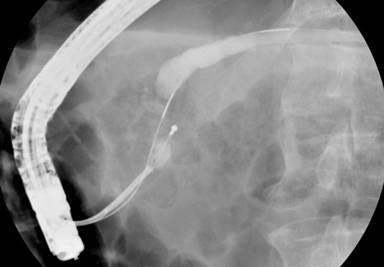

A residual 8 mm stone fragment was captured in a basket for mechanical lithotripsy. However, it was too hard for the metal sheath to crush. While attempting to crush the stone by applying traction, the basket wires fractured near the lithotripter handle outside the patient’s mouth. The stone and basket thus became impacted inside the patient’s pancreatic duct (Figure 1).

|

Figure 1. Basket impaction of pancreatic duct stone during mechanical lithotripsy. |